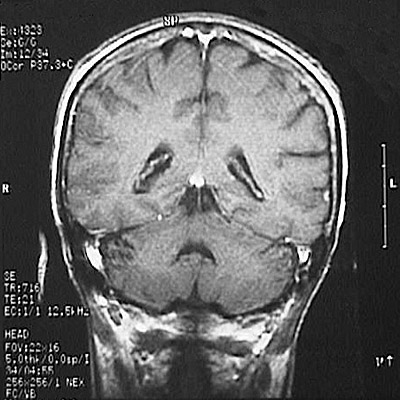

This is a normal coronal T1 weighted enhanced MRI scan demonstrating the parietal lobe and occipital lobe and cerebellar hemisphere and fourth ventricle and superior sagittal sinus and sigmoid sinus and occipital horn of lateral ventricle and choroid plexus.